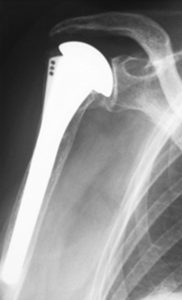

Hemi means half, and arthroplasty means joint replacement. Hemiarthroplasty is a surgical procedure that replaces one end of a bone on one side of a joint with a prosthesis, while leaving the other half intact. It is the treatment for some fractures of the hip and shoulder.

- Severe 4 part or 3 part shoulder (proximal humeral) fractures